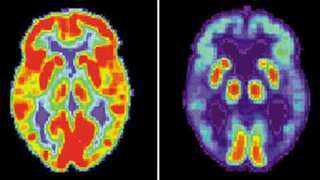

19-year-old Chinese becomes youngest to be diagnosed with Alzheimer’s disease